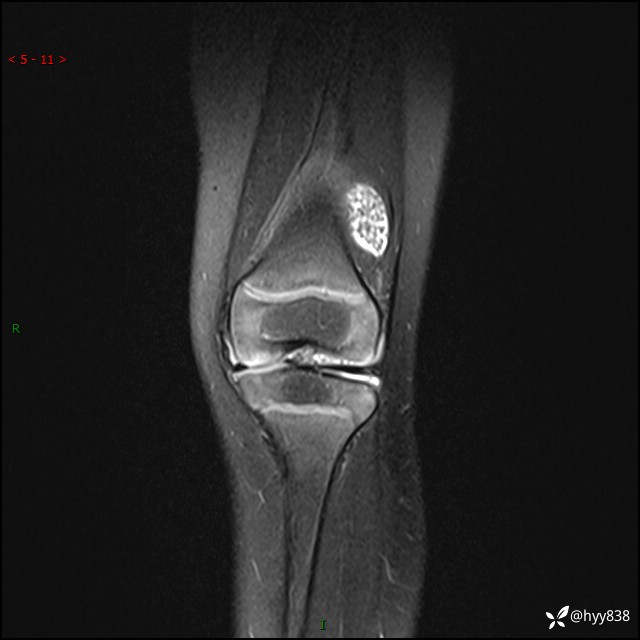

不到2岁小女孩,左下肢跛行1月。白班偶遇,经典分享---(有结果)

现病史:患儿1月前无明显诱因出现左下肢跛行,伴左膝关节红肿,无发热、咳嗽、恶心、呕吐等症,于当地医院就诊行X线片未提示异常,今至我院门诊就诊,门诊医师拟“跛行待查”收入院。 病后,患儿精神、食欲可,睡眠欠安,大小便通畅,体力体重无明显下降。

左膝MRI平扫